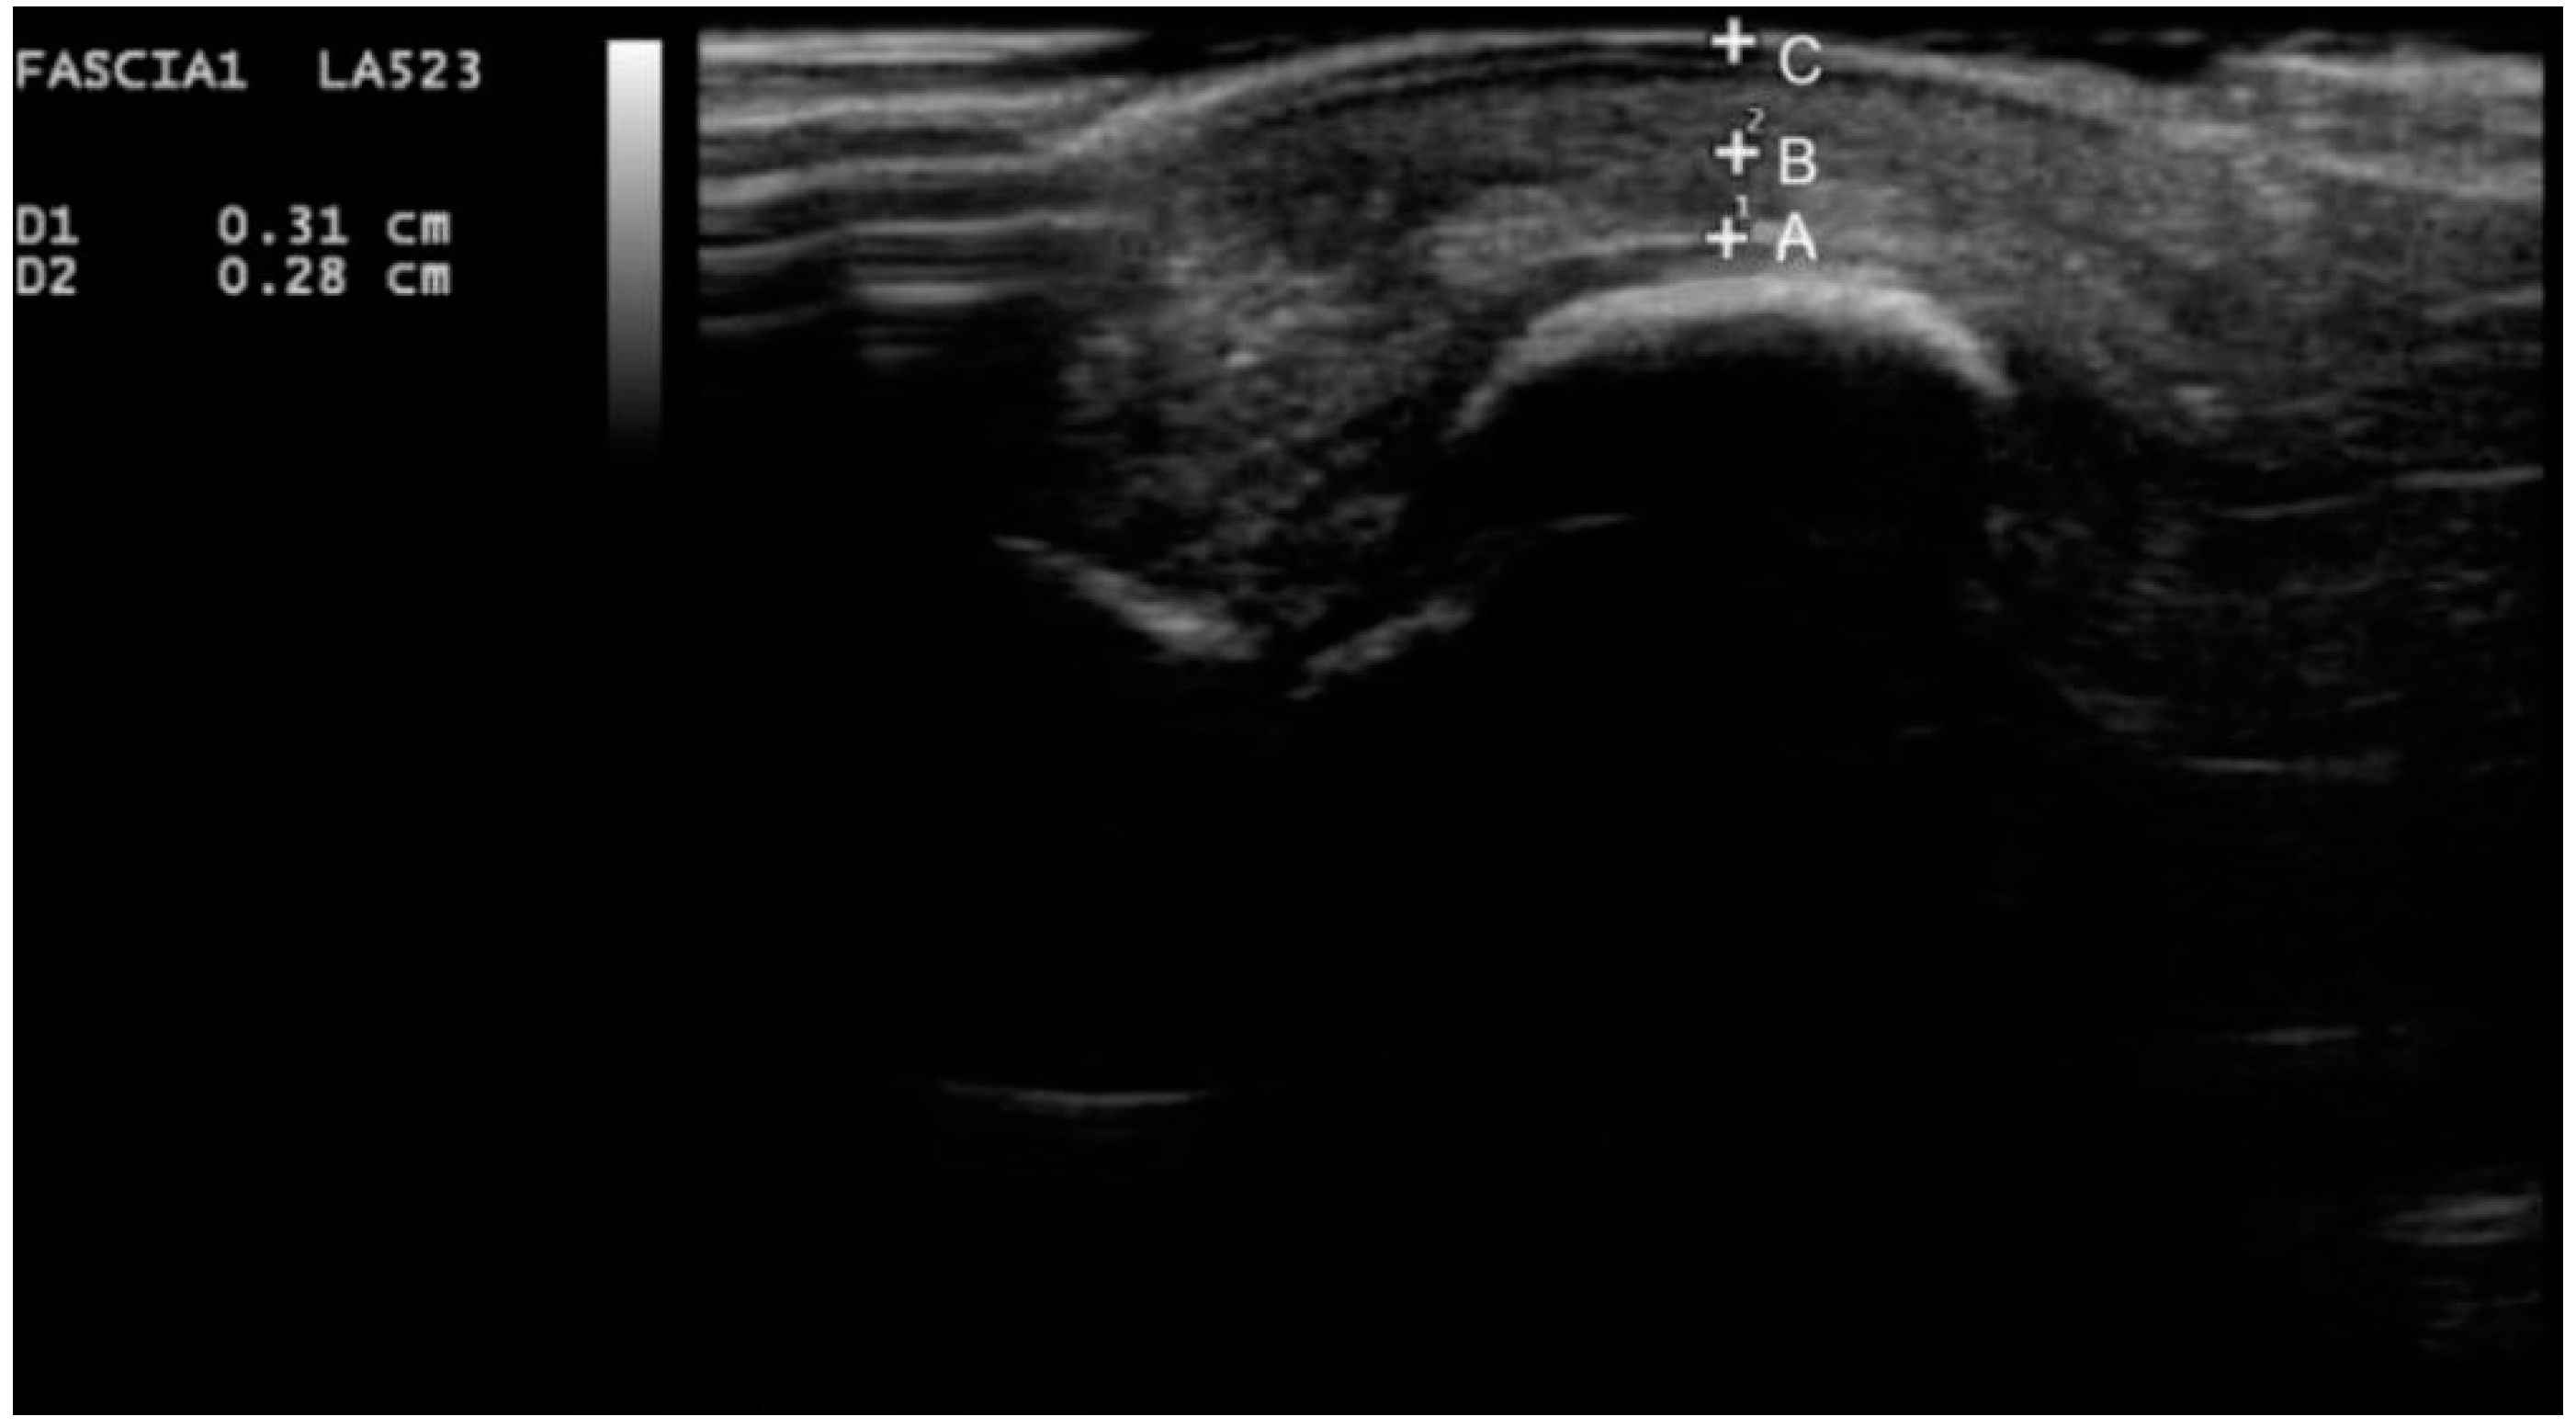

A 7–12 mHz linear-array ultrasound transducer (MyLab 25 Gold model; Esaote SpA., Firenze, Italy) was used for assessing the soft tissue morphology. Participants were placed in a supine position with the ankle in a neutral position. Calluses were removed if necessary. A generous amount of ultrasound gel was placed between the skin and the transducer to avoid compressing the skin surface. The first and second metatarsals were measured to determine the plantar soft tissue thickness, as they are considered to be more reliable metatarsal areas and have lower statistical heterogeneity [23]. The ultrasound transducer was placed perpendicularly to the sesamoid bones and the second metatarsal head, and a longitudinal section of both the sub-metatarsal skin and the fat pad was obtained to measure the first and second metatarsal heads, respectively. First, metatarsal skin and fat pads were defined as the average of the measurements of the lateral and medial sesamoid [24]. The changes in the echogenicity of the ultrasound image on each sonogram were used to identify the soft tissue layers (Figure 1).

Figure 1.

Ultrasound image of the sub-metatarsal skin and fat pad thickness under the medial sesamoid. Point A to point B, representing the thickness of the sub-metatarsal fat pad; point B to point C, representing the thickness of the sub-metatarsal skin.